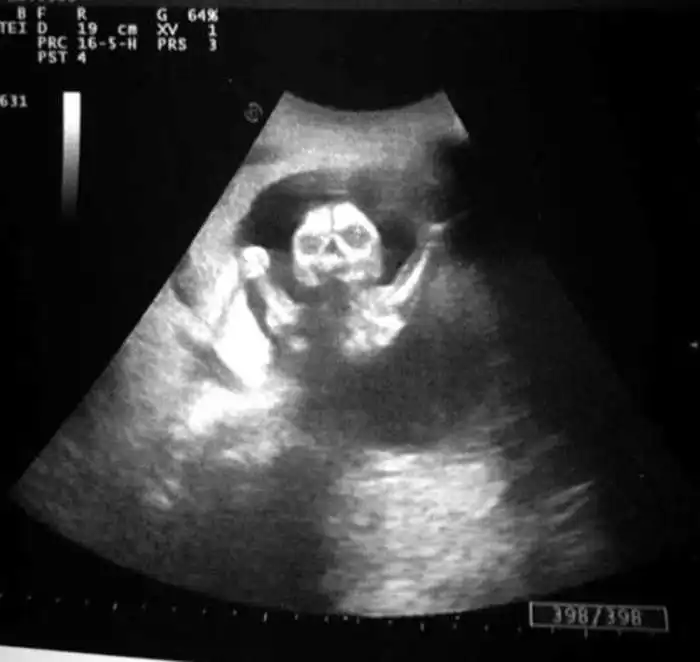

На экранах аппаратов УЗИ дети, находящиеся в утробе матери, выглядят далеко не такими милыми и симпатичными, какими они оказываются после своего рождения.